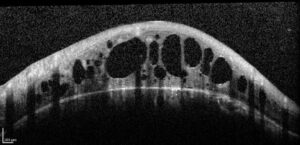

Exame de OCT alterado mostrando edema cistóide:

Edema Cistoide no exame de OCT